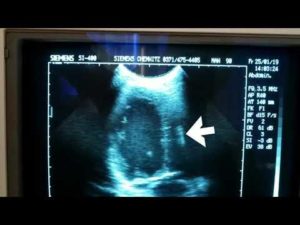

- УЗИ – если датчик прибора необходимо проводить над областью постановки электкрокардиостимулятора.

Необходимо заметить, что эхокардиография и УЗИ исследования вне зоны кардиостимулятора выполнять не запрещено.

- запрещается проводить ультразвуковое исследование (УЗИ) с направлением луча на корпус стимулятора;

При необходимости ультразвукового исследования необходимо избегать направления луча на корпус кардиостимулятора. Флюорографию и рентген проходить можно. Более того, рентгенография – первое исследование, которое назначают при подозрении на поломку электрода.